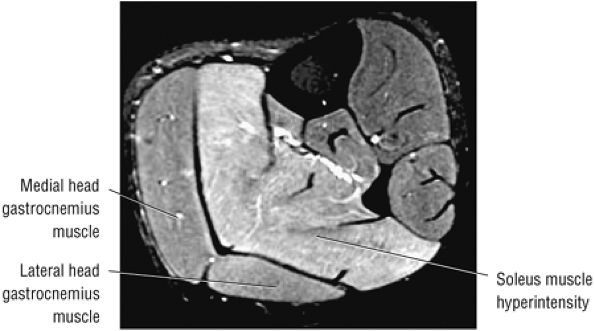

FIGURE 5.128 ● Grade 1 soleus muscle strain secondary to an Achilles rupture. Axial FS PD FSE image.